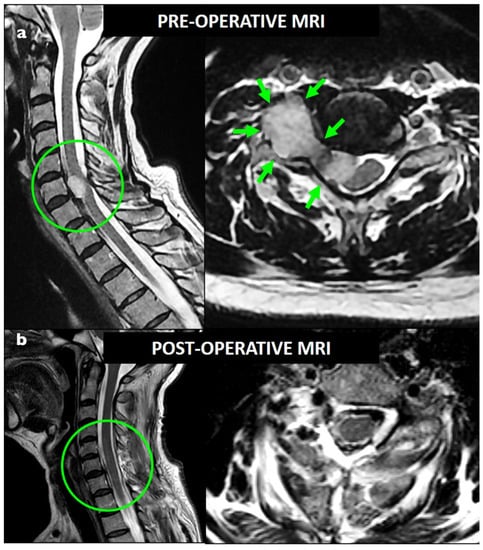

Figure 1. Preoperative (a) and postoperative (b) T2-weighted MRI showing a foraminal C7 dumbbell schwannoma (Sridhar class IVa); GTR was obtained with a single-stage posterior approach.

Careful dissection of the surrounding nerve rootlets and roots was performed in order to identify and sacrifice exclusively the parent spinal root. Once the parent nerve root was identified, complete resection was performed at the most distal and proximal point at the junction between the lesion and the nerve (Figure 1 and Figure 2). The intracanal and foraminal part was successfully resected in all cases. GTR resection was achieved in 22 patients (84.6%) and was obtained with a complete en bloc resection in 18 cases (69.2%). Four patients (15.4%) with a huge paraspinal component (3 Sridhar grade IVB and 1 grade V) had STR. The residual part was paravertebral in all cases. No second-stage surgery was considered necessary in these cases according to the clinical context, and no progression was observed at follow-up. Surgical complications occurred in four (15.4%) patients: two CSF leaks and two wound infections. All required surgical management. The mean postoperative follow-up was 22.4 months (range 6–85 months). No recurrence was observed.